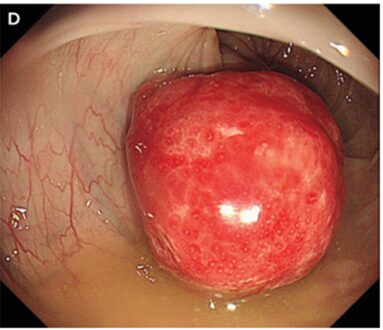

その後、結腸内視鏡検査が施行され、2.5㎝の有茎性ポリープが明らかになり、これが腸重積のリードポイントであると考えられた。

ポリープ切除が行われ、病理組織機検査では過誤腫であることが判明した。